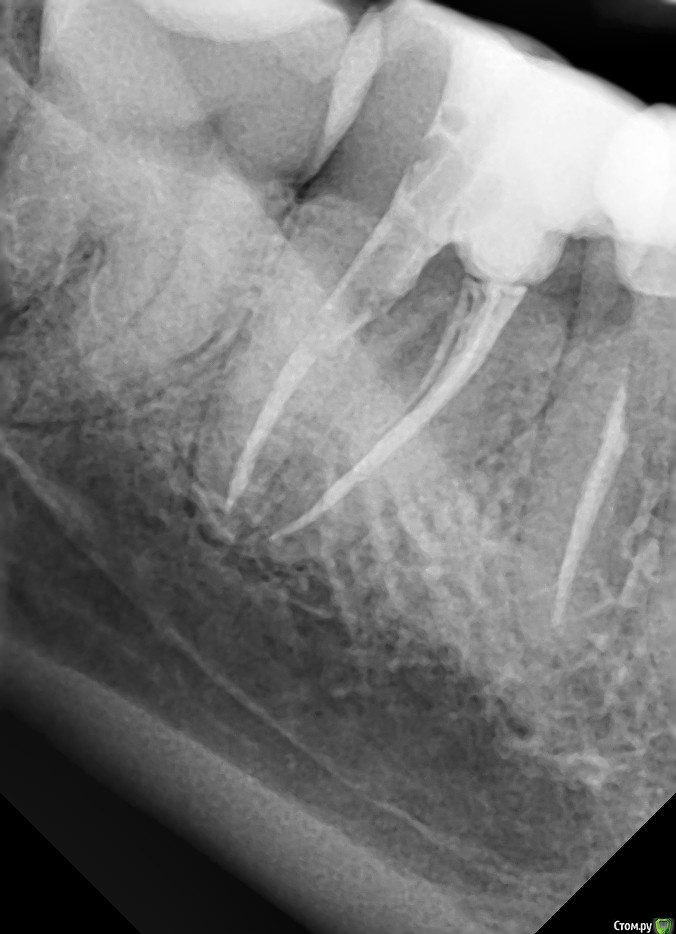

-Алексей- Опубликовано 22 декабря, 2018 Поделиться Опубликовано 22 декабря, 2018 Зуб депульпирован 3 месяца назад. На данный момент под ним периодически ноет и кровоточит десна (совсем чуть-чуть). Врач у которого лечил говорит что всё нормально. Другой врач сказал что возможно есть перелом и придётся удалять. Каковы шансы сохранить зуб? Ссылка на комментарий

St. Опубликовано 22 декабря, 2018 Поделиться Опубликовано 22 декабря, 2018 Добрый день. По снимку каналы заполнены хорошо, штифт на месте. Явного перелома не вижу, но они и не всегда видны, к сожалению. Понаблюдайте пока за зубом,пока покажитесь парадонтологу( доктор который занимается чистками и лечит десну) чтобы исключить проблемы с десной. Если все пройдет после лечения десны, все хорошо. Если же ничего не изменится, или со временем будет болеть сильнее и диагноз перелом корня подтвердиться, тогда только удаление. Ссылка на комментарий